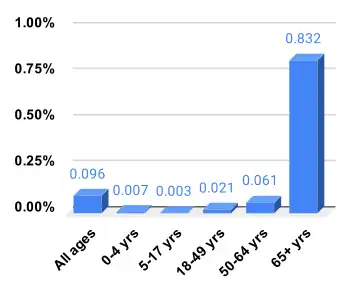

Mortality

Every year about 290,000 to 650,000 people die due to influenza globally, with an average of 389,000.[187] In the developed world most of those who die are over the age of 65.[1] In the developing world the effects are less clear; however, it appears that children are affected to a greater degree.[1]

Although the number of cases of influenza can vary widely between years, approximately 36,000 deaths and more than 200,000 hospitalizations are directly associated with influenza a year in the United States.[188][189] One method of calculating influenza mortality produced an estimate of 41,400 average deaths per year in the United States between 1979 and 2001.[190] Different methods in 2010 by the Centers for Disease Control and Prevention (CDC) reported a range from a low of about 3,300 deaths to a high of 49,000 per year.[191]